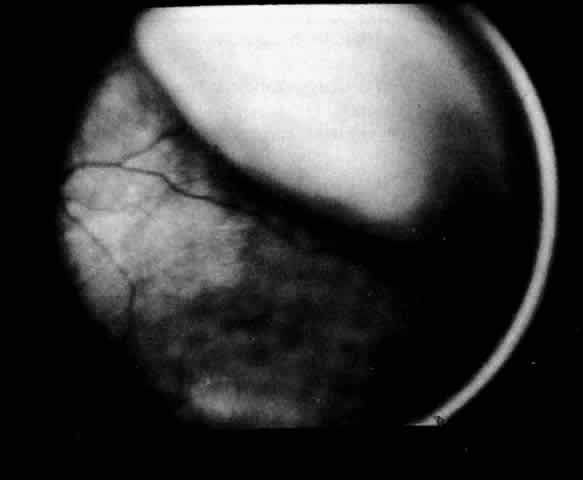

| The presence of certain clinical characteristics may assist in the diagnosis

of a ciliochoroidal effusion (Table 1). One clinical feature is choroidal edema. Choroidal edema may resemble

a retinal detachment to a hasty observer; however, darkness of the uvea, lack

of tremulousness, and normal retinal vessels indicate a probable

uveal process (Fig. 1). The effusion may extend under the pars plana, allowing visualization

of the ora serrata without scleral depression (Fig. 2).9 As shown in Figure 2, the surface of the elevation is convex and smooth, with a solid appearance

and a homogeneous grayish color. A shallow anterior chamber and

a low intraocular pressure may also suggest the diagnosis. Myopia in the

presence of anterior displacement of the lens-iris diaphragm may be

another diagnostic clue.10,11